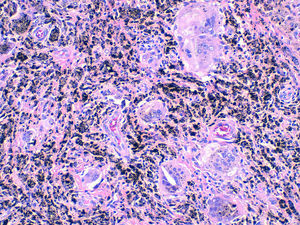

Mujer de 72años, con antecedentes de artroplastia unicameral de rodilla derecha desde hacía 12años, que acude a nuestra consulta por dolor en dicha rodilla de 6meses de evolución, sin fiebre ni síntomas sistémicos. En la exploración física se objetivó tumefacción de dicha rodilla. La radiografía mostró prótesis parcial en el compartimento medial, sin alteraciones (fig. 1). Se realizó artrocentesis, obteniendo un fluido oscuro (fig. 2), con 150 células (75% polimorfonucleares), glucosa 90mg/dl, proteínas 2mg/dl. El cultivo del líquido articular fue negativo. Con la sospecha de metalosis, la paciente fue derivada a la consulta de traumatología, y la prótesis fue sustituida por una prótesis total. Una muestra de tejido sinovial fue enviada a anatomía patológica, mostrando macrófagos con pigmento negruzco en su citoplasma y linfocitos (figs. 3 y 4). Actualmente la paciente se encuentra asintomática.

La metalosis se define como una corrosión debida a la erosión de los componentes metálicos, que producen partículas que inducen una reacción de hipersensibilidad. Generalmente es asintomática y la aparición de dolor o rigidez se debe al aflojamiento secundario de la prótesis1. Su sospecha puede surgir al apreciar zonas osteolíticas lobuladas con o sin aumento de los tejidos blandos adyacentes en la radiografía simple, debiendo realizarse diagnóstico diferencial con movilización aséptica de la prótesis y con artritis séptica2. Macroscópicamente aparece una pigmentación negruzca de la articulación junto con un líquido sinovial oscuro. Microscópicamente podemos apreciar partículas metálicas, ya sean libres o absorbidas por macrófagos, con un infiltrado linfocitario que sugiere una respuesta inmune3. El tratamiento consiste en el reemplazo de la prótesis y la realización de una sinovectomía con el fin de eliminar las partículas metálicas3.